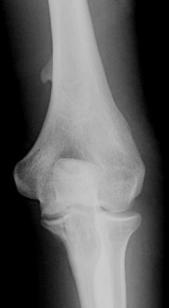

Diagnosis?

Bone Infarct